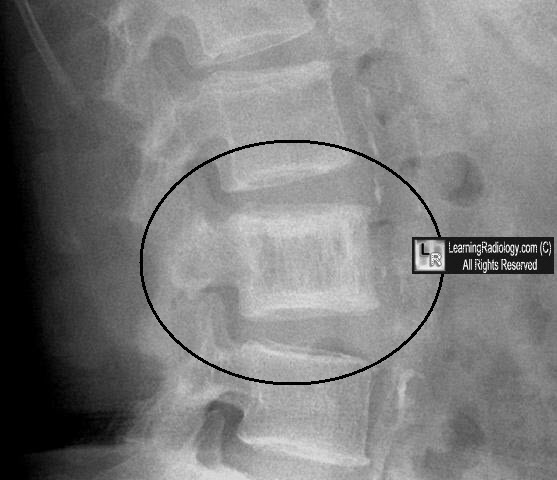

Dr. James Paget described this disease in 1877, nearly 20 years before the invention on x-rays. It is a tumor-like process that causes osteolysis followed by extensive attempts to repair resulting in an increased thickness of the bone's cortex.